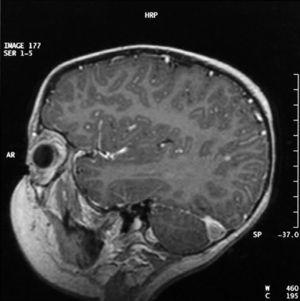

Se le realizó un hemograma (leucocitos 6.000/μl, neutrófilos 51 %, resto normal), bioquímica sérica y coagulación (proteína C reactiva 12 mg/l, procalcitonina 0,11 ng/dl [normal < 0,5 ng/dl], resto normal). El líquido cefalorraquídeo tenía una presión de apertura aumentada (> 20 mmHg), con citoquimia normal, cultivo y estudio de virus neurotropos negativos. En la TC de mastoides y cráneo se objetivó una otomastoiditis derecha con trombosis de los senos venosos transverso y sigmoide derechos y vena yugular derecha (fig. 1).

Figura 1.TAC craneal. Signo del delta vacío.

El diagnóstico se debe confirmar radiológicamente, mediante TC craneal, que demostrará una otitis complicada, y el signo clásico del "delta vacío" sobre todo si el seno afectado es el sagital superior 2. Más específica es la angio-RM, que debe combinarse con la RM con gadolinio para estudiar la existencia de otras complicaciones cerebrales.